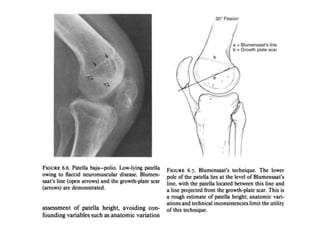

A patella alta , or high-riding patella, is a patella that is too high above the

trochlear fossa and occurs when the patellar tendon is too long.

Patella alta is considered a main factor in patellofemoral misalignment

because with patella alta, the degree of flexion needs to be higher for the

patella to engage in the trochlea, compared with a normal knee.

This problem leads to reduced patellar contact area and decreased bone

stability in shallow degrees of flexion.

About 25% of the patients with acute patellar dislocation have a high-riding

patella depicted on MR images.

Note, however, that patella alta is a normal anatomic variant that is

asymptomatic in most individuals.